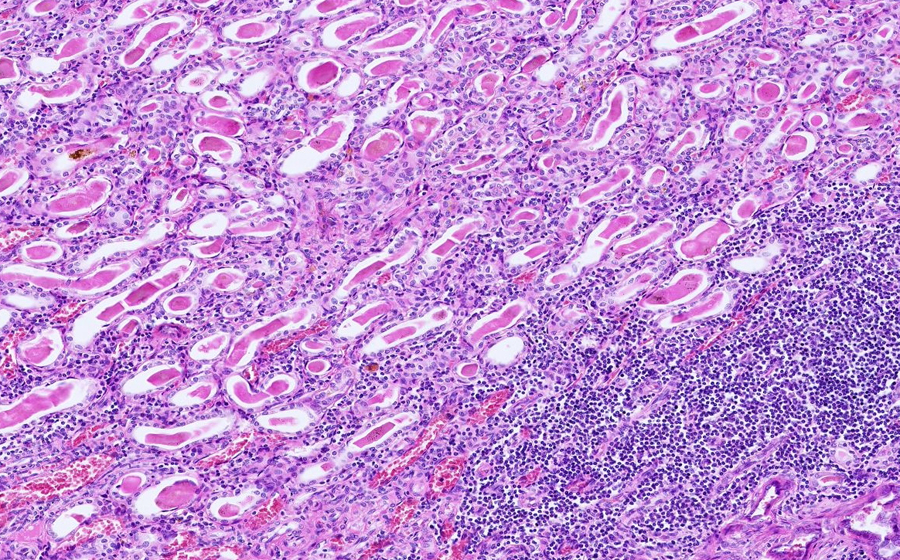

Slide 3: Glomerulonephritis - chronic

Histologic section of kidney from a patient with chronic glomerulonephritis. (click here to review normal tissue)

Image 3 - 50X

Slide 3 - Image 3